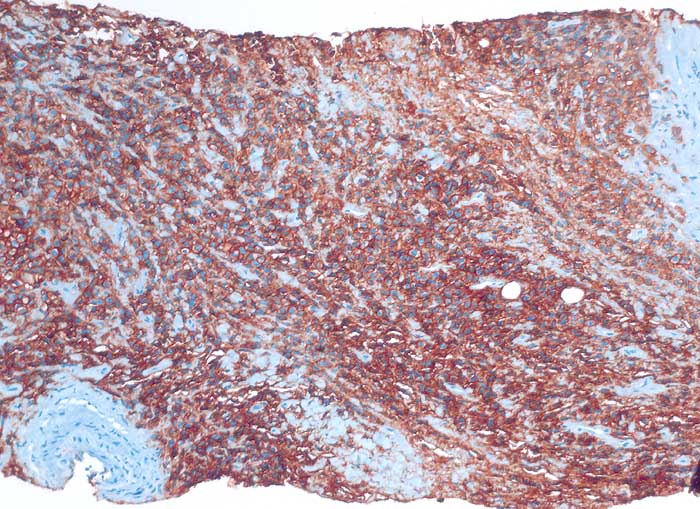

diffuses grosszelliges B-Zelllymphom

Nierenbecken

Nierenhilusweichteile: die Tumorzellen reagieren membranär positiv mit dem B-Zell Marker CD20.

Nieren-Tumor rechts. DD: Urothel-Ca.

Histologie

Immunhistochemie

CD20 (L26)

100